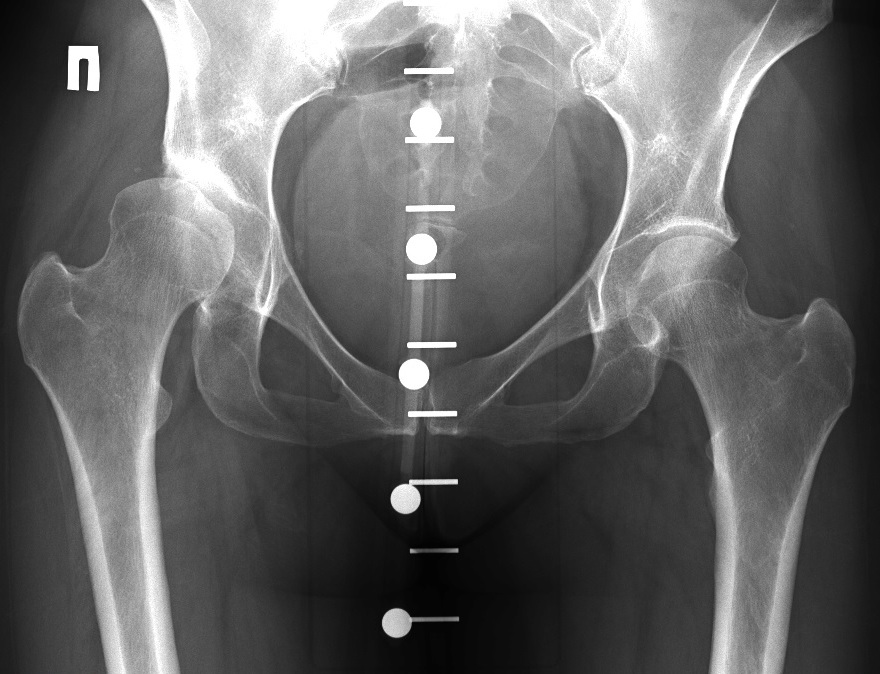

Рентгеновские снимки: Синовит тазобедренного сустава